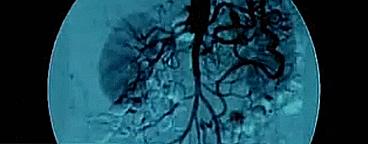

在他的实验室中,挂着一张人体肺部血管图,这是他最得意的作品

在没有这张图之前,医生们并不知道人体肺部的血管分布情况

肺循环中的毛细血管分布十分广泛,微动脉呈多向分布,形成多个肺泡毛细血管片

通过传统的解剖学手法,很难将肺部血管的分布弄清楚

可是肺部血管受力异常,可能会引起一种极为严重的疾病——肺动脉高压

冯元桢通过建立肺毛细血流片层流动(Sheet flow)模型

研究出了肺血流动力学的规律

从而建立了肺部血管的分布情况图

肺毛细血流片层流动模型:

在肺循环中,小动脉与小静脉之间的毛细血管位于肺泡间隔膜的中间,形成非常密集的血管网。

在这种毛细血管中流动的血液可以视为由两弹性薄膜所限定的血液薄片,当血压增大时,薄膜会鼓起来,薄片的厚度也将增大。这些毛细片的长度与横向尺寸几乎是同一数量级。

与体循环不同的是,体循环的毛细血管由于被周围组织所包围,可认为是刚性的,而肺循环的毛细片的上、下两壁与肺泡相邻,则富有弹性。

而事实证明,这张肺部血管分布图为临床疾病的诊断与治疗提供了极大的帮助,这让冯元桢感到十分的欣慰